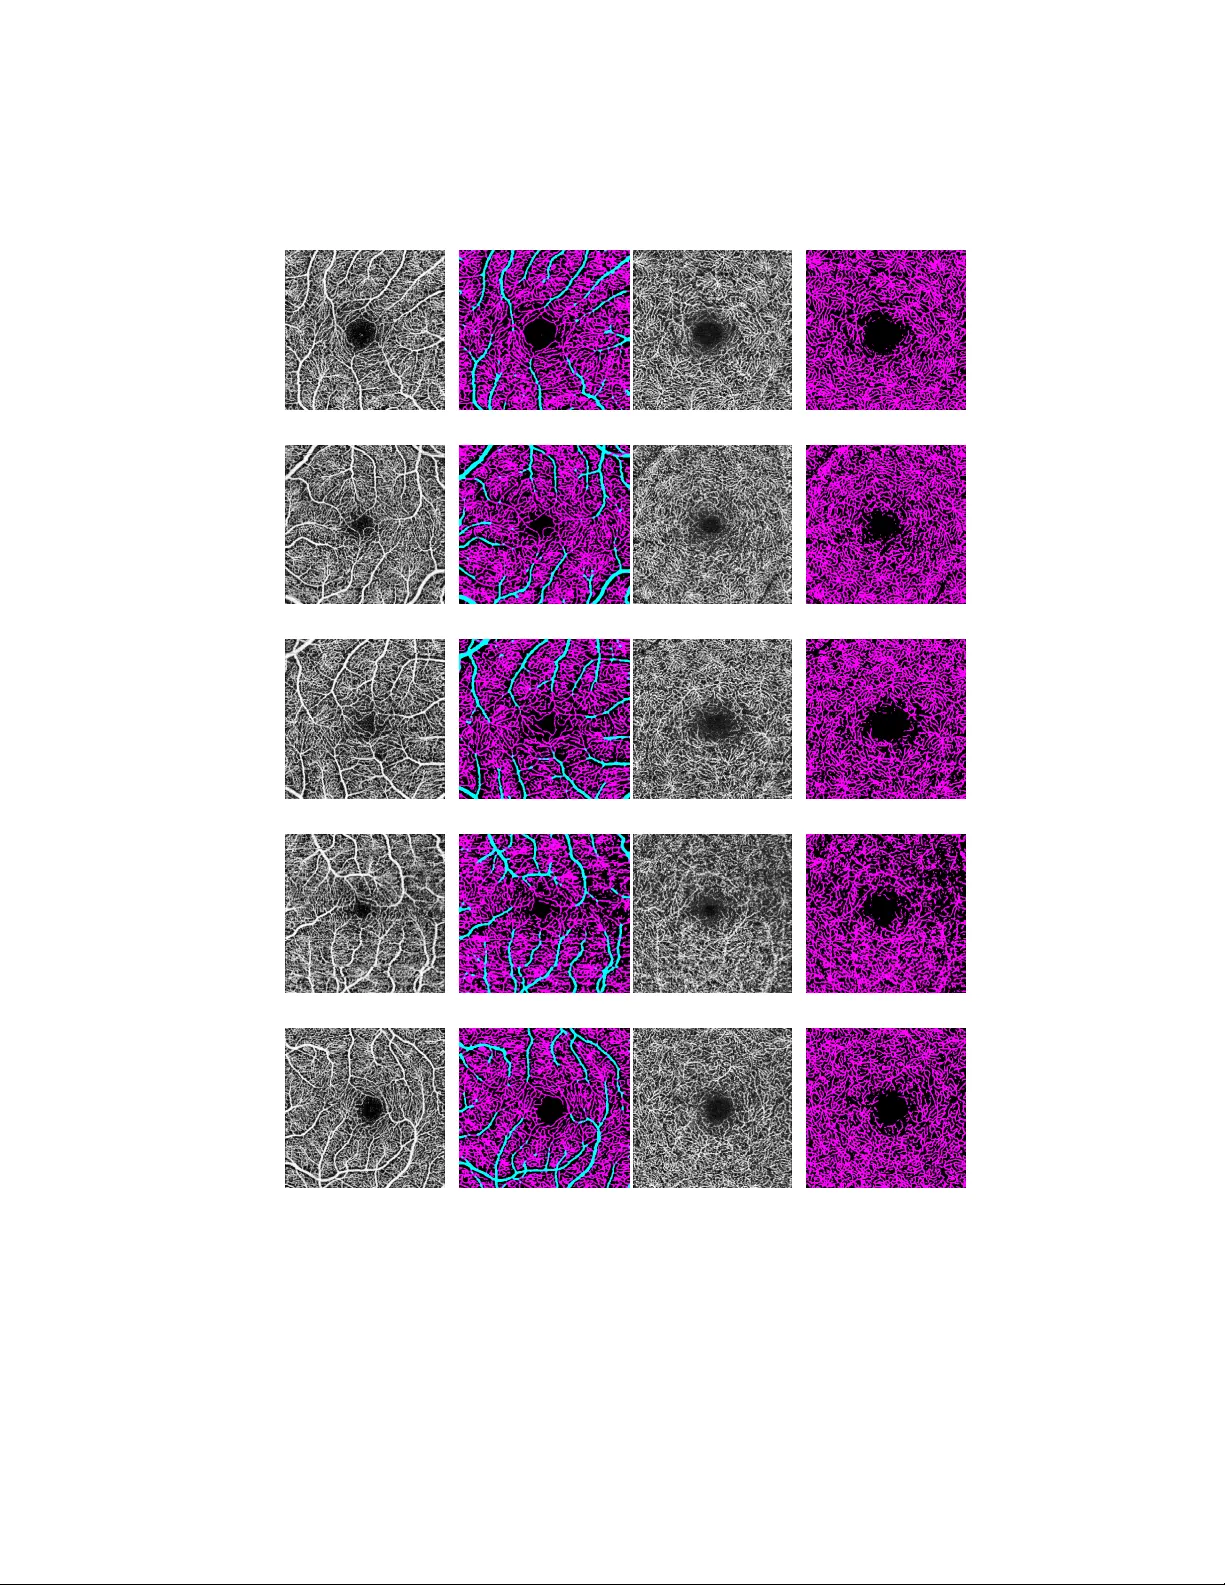

Dictionary-based Metho d for V ascular Segmen tation for OCT A Images Astrid M. E. Engb erg, V edrana A. Dahl, and Anders B. Dahl T echnical Univ ersity of Denmark, Kgs. Lyngby , Denmark { asteng,vand,abda } @dtu.dk Abstract. Optical coherence tomograph y angiography (OCT A) is an imaging tec hnique that allows for non-in v asive inv estigation of the mi- cro v asculature in the retina. OCT A uses laser light reflectance to mea- sure moving bloo d cells. Hereby , it visualizes the blo od flow in the retina and can b e used for determining regions with more or less blo o d flow. OCT A images contain the capillary netw ork together with larger bloo d v essels, and in this pap er we propose a metho d that segments larger v essels, capillaries and background. The segmentation is obtained using a dictionary-based mac hine learning metho d that requires training data to learn the parameters of the segmentation mo del. Here, w e give a de- tailed description of how the metho d is applied to OCT A images, and w e demonstrate ho w it robustly lab els capillaries and bloo d vessels and hereb y provides the basis for quantifying retinal bloo d flow. 1 In tro duction Optical coherence tomograph y angiograph y (OCT A) is a relatively no v el imaging metho d commercially a v ailable in 2014 [16]. Compared to alternative retinal imaging modalities, it is fast and pro vides high-resolution, depth-resolved images of the retinal microv asculature without any inv asive pro cedures such as contrast agen ts [12]. Despite the rapid acquisition, images can easily b e corrupted by motion artefacts and noise. Noise induced by a lo w signal-to-noise ratio can o ccur due to eye conditions such as cataract [16], where the laser light, that illuminates the retina as part of the OCT A imaging system, is scattered by the cataract-affected lens. F urthermore, the image intensit y in OCT A images can v ary o ver the image plane and giv e rise to bias in the image. These effects m ust b e accoun ted for when choosing a metho d for obtaining an automatic segmentation of the retinal micro v asculature. OCT A imaging is a 3D acquisition metho d [12], but the clinical scanners emplo yed in our studies perform a preprocessing of the data that segments the v olume into so-called en face angiograms of different retinal lay ers. W e fo cus on t wo lay ers: the sup erficial retinal lay er (SRL) and the deep retinal lay er (DRL). An example is shown in Fig. 1. Here, the larger blo o d vessels (arterioles and v enules) are seen as thick er bright structures and the capillary netw ork is a finer net work of bright structures b et w een the larger vessels. The dark area in the middle is the fo veal av ascular zone (F AZ). 2 A. Engb erg et al. (a) (b) Fig. 1. Example of an OCT A image including (a) the superficial retinal la yer (SRL) and (b) the deep retinal lay er (DRL). The problem w e address is to segmen t OCT A images in to three classes includ- ing larger vessels, capillaries, and background. By distinguishing b et ween larger v essels and capillaries, the t wo structures can be analyzed separately . This allo ws for removing the influence of the size of the larger vessels, when quantifying the retinal capillaries, and hence not ov erestimating their density . W e will solve this as a pixel lab eling problem, such that we assign each pixel to one of three lab els using a dictionary-based segmen tation metho d. The ma jorit y of clinical studies focus on solely obtaining quantitativ e metrics of the microv asculature, and segmentation of the microv asculature from OCT A images is a problem that has b een addressed in only a few studies. Most studies obtain a segmen tation through thresholding and filtering schemes [1,13]. A few studies utilize man ually annotated data to create segmentation mo dels, such as probabilistic mo dels [8], conv olutional neural netw orks [15], and Hessian- and deep learning-based metho ds [6] to segmen t all vessels. A single study [6] au- tomatically segments main vessels and capillaries separately in retinal images using deep learning. One anatomical difference betw een larger vessels (arterioles and ven ules) and capillaries is their thic kness. While the diameter of the capillaries is around 4-9 µ m [12] and is determined b y the size of the red bloo d cells, the larger vessels are thic ker than capillaries and they v ary more in size. Since the larger v essels and capillaries are connected, it is not trivial to design a model that separates the t wo anatomical structures. It cannot b e accomplished by a simple thresholdning metho d, whic h are commonly applied to OCT A data. Instead, we propose to use the dictionary-based segmen tation metho d from [2,3,4], where the segmentation mo del is learned from annotated training data. W e ha ve used this metho d for segmen ting retinal microv asculature from OCT A images in [9,10,11]. Dictionary-based Segmentation 3 Fig. 2. Illustration of the pipeline for the dictionary segmen tation method. It consists of a training and a segmentation part. The training is based on a training image with a corresp onding label image. Here, the training labels are blue for larger v essels, red for capillaries, and black for background. Based on patches sampled in the training image we p erform a clustering (T1), whic h makes up the dictionary . Dictionary lab el patc hes are computed from the clustering of the training image and the lab el image (T2). In the segmentation part, w e assign the dictionary to an input image (S1) and then compute pixel-wise probabilities of the lab els using the dictionary lab els (S2). Finally , we obtain the segmentation illustrated here. Larger vessels are marked with cy an, capillaries are magenta, and bac kground is black. W e in tro duced the fundamen tals of the dictionary-based segmentation metho d in [2]. It has later b een extended for efficient computation of lab el probabilities whic h allow ed iteratively up dating lab el probabilities, which we used for com- puting deformable b oundary mo dels in [3,4], where probabilities are computed in each iteration. F urther, we extended the mo del to allow for interactiv e seg- men tation in [5], which allows for computing lab el probabilities from partially annotated data. In this pap er we will fo cus on details related to segmenting microv asculature from OCT A images. Core elements of the metho d are describ ed in e.g. [5], but to give a complete description of the metho d we will also describ e them here. F urthermore, we use a feature-based representation to characterize local texture instead of using intensit y patches. This has not previously b een described, so we will pro vide the details here. 4 A. Engb erg et al. 2 Metho d The basic principle of the dictionary-based segmentation mo del was introduced in [2], which is inspired by sparse co ding metho ds [7]. Sparse co ding metho ds op erate on image patc hes, and were originally applied to problems like denois- ing and texture mo deling. Our dictionary-based segmen tation metho d is similar to sparse co ding metho ds b ecause it emplo ys a dictionary of image patc hes. Ho wev er, here we assign each patch to only one dictionary elemen t, which is differen t from sparse co ding, where an image patc h is t ypically represented by a small n umber of dictionary patches. The idea of our method is that image patches with similar appearance should ha ve the same lab el. W e exploit this idea by clustering image patc hes (unsup er- vised part of training), computing patc h label information from user input on the training image (sup ervised part of training), and then pasting this information in a testing image (using the mo del). An ov erview of our segmen tation pip eline is sho wn in Fig. 2. 2.1 T raining the mo del F or training the segmentation mo del we need training data, consisting of image data and user-provided lab eling. The image data used for training needs to b e represen tative of the segmentation problem. This is usually one image or a small set of images. User-provided lab eling should provide the desired segmentation for the images. It is not a requirement that all image data used for training is lab eled by the user, but lab eling should co ver the v ariability of the structures to b e segmented. Extracting patc h v ectors. W e aim to construct a feature descriptor c harac- terizing the lo cal app earance around ev ery image pixel. W e start b y extracting an N × N patc h around the pixel. W e choose N to be odd suc h that the patch can b e centered on a pixel, and we rearrange the patch into a vector of length N 2 . Reducing the dimensionality of the patc h v ectors. W e preform principal comp onen t analysis (PCA) to reduce the dimensionality of the patch vectors. Here, we randomly select K patc h vectors of length N 2 , denoted v k . F or this set of vectors we compute a mean ¯ v , such that we can compute patch vectors cen tered in origo v k − ¯ v , and arrange those vectors in the rows of a matrix V , whic h will hav e size K × N 2 . No w, we p erform eigendecomp osition of a matrix U = V T V , (1) and keep eigenv ectors corresp onding to q largest eigenv alues in a N 2 × q matrix S . F or each image pixel i and its patc h vector, we can now compute the pro jec- tion f i = ( v i − ¯ v ) T S , and use it as a feature vector of length q . Dictionary-based Segmentation 5 (a) I (b) I x (c) I y (d) I xy (e) I xx (f ) I yy Fig. 3. Subfigures sho wing the comp onen t with the largest v ariability of the lo cal features of the raw intensities, I , and the first ( I x , I y ) and second order deriv atives ( I xy , I xx , I yy ) with a feature patch size of 7 × 7 pixels. Incorp orating image deriv ativ es. W e strengthen the features emplo yed in our metho d b y incorp orating the v alues of the first and second deriv atives of the image I x = ∂ I ∂ x , I y = ∂ I ∂ y , I xx = ∂ 2 I ∂ x 2 , I xy = ∂ 2 I ∂ x∂ y , I y y = ∂ 2 I ∂ y 2 . (2) F or eac h of these five images we follow the pro cedure as described for the intensit y image I , i.e. patch vector extraction and dimensionality reduction using PCA. This results in five additional feature vectors of length q . When all these are concatenated, we are left with a 6 q feature vector p er every image pixel. The PCA feature vector describ es the local appearance of the image around the pixel. Fig. 3 illustrates the PCA features computed in an OCT A image. Clustering. The PCA feature vectors are clustered using a k -means hierar- c hical clustering to obtain the dictionary . As a distance measure, w e use the Euclidean distance b et w een PCA feature patches. Hierarc hical clustering is chosen instead of a conv en tional k -means because it sp eeds up the clustering dramatically . This allo ws for large dictionaries, and giv es a very efficient search structure for assigning new feature vectors to the dictionary . 6 A. Engb erg et al. The k -means hierarc hical clustering is go verned by tw o parameters, a branc h- ing factor b and a depth t . A set of feature vectors is clustered by first clustering all vectors to b clusters using conv entional k -means, and then clustering each of these groups into b sub-clusters. This is rep eated t times or until there are less than b feature vectors in a cluster. The result is a tree graph, the k -means tree, where the no des represent cluster centers. F or our purp oses, clustering is p erformed on PCA feature v ectors corresp ond- ing to patches extracted from the training image. W e therefore exp ect that fea- tures b elonging to the same cluster corresp ond to image patches whic h hav e a similar app earance. Incorp orating user lab elings. As mentioned previously , w e exp ect similar image features to hav e similar lab els. Having computed clusters of the image features, w e need to define a lab eling for each cluster. F or this we need user lab elings. This step constitutes the sup ervised part of building the dictionary . F or an image of the size n × m , user lab elings are stored as an n × m × C arra y L , where C is the num b er of lab els. In our case C is three since we are in terested in larger vessels, capillaries and background. Elemen ts of L are binary , suc h that each pixel p osition b elongs to only one lab el, indicated by a v alue 1 in one la yer of L . W e now compute lab eling information for eac h cluster in the dictionary by com bining lab eling information of all the members of the cluster. F or this we extract patches of size M × M × C from L , where M is chosen to b e o dd such that patc hes are centered on a pixel. F or each dictionary cluster, w e extract suc h patches at the same spatial lo cations as the image patches b elonging to the cluster. This set of patc hes is then a veraged, and we obtain lab eling information for each dictionary cluster. Due to the av eraging of binary v alues, lab eling information asso ciated with dictionary patc hes is not binary , but can rather b e interpreted as probabilities. 2.2 Using the mo del Once we ha ve a dictionary and the dictionary probabilities, w e can use our mo del to pro cess a new image (a testing image) and obtain pixel-wise probabilities of b elonging to each of C lab els. Dictionary assignmen t. The first step in pro cessing the testing image is dic- tionary assignmen t. F or this, w e first extract a PCA feature vector from the patc h around the pixel. Then we search the k -means tree to assign the pixel to the dictionary cluster. Our assignment is done b y a simple greedy searc h through the k -means tree, and then assigning a feature vector to the nearest no de in the tree. This do es not guarantee that the feature vector is assigned to the closest no de in the tree, but will generally ensure that similar patterns are group ed together. An illustration of the assignmen t is shown in Fig. 4a. Dictionary-based Segmentation 7 (a) Assignment image (b) Probabilit y image for larger vessels (c) Probability image for capillaries (d) Probabilit y image for background Fig. 4. Here, we show an assignment image in (a), where the color is the index of whic h dictionary element the patch around that pixel is assigned to. W e also sho w the resulting probability images for the three differen t classes (b-d). Computing probability image. F rom the dictionary assignment, we build a probabilit y image P of size n × m × C by visiting all image pixels for eac h lab el, obtaining the probability information asso ciated with their dictionary cluster, and adding it to P in the spacial p osition corresp onding to the pixel. Finally , w e normalize P suc h that the C lab el probabilities sum to one. T o capture the lo cal app earance of the image, it can sometimes b e adv an- tageous to c ho ose a sligh tly larger patch for computing the feature vector than the label patch, meaning that N > M . In that case, the ( N − M ) / 2 b oundary pixels will not b e lab eled. But in practice, this does not influence our analysis. Ho wev er, M and N can b e chosen indep enden tly such that it makes sense for the giv en segmentation problem. The final step b efore obtaining the segmentation is to choose the most prob- able lab el from the C lab els. 3 Exp erimen ts T o train the mo del, w e are using one OCT A image (a training image) with cor- resp onding lab eling, b oth shown in Fig. 5. The OCT A image has b een acquired 8 A. Engb erg et al. b y a sw ept source DRI OCT T riton, T op con Medical Systems, Inc. The image w as initially 320 × 320 pixels, but was upscaled by a factor of tw o to a final size of 640 × 640 pixels. Before using the image to train the dictionary , we applied an adaptive histogram equalization, which impro ved the contrast of the image [14]. F or adaptive histogram equalization the image is divided into patches of size 40 × 40 pixels with a contrast enhancement limit of 0.004 prev enting ov er- saturation in homogeneous regions. The three classes for describing the retinal micro v asculature include cap- illaries, larger v essels (arterioles and ven ules), and background. Larger vessels are defined as v essels with a radius of at least t wice the radius of the capillar- ies. Image patches for computing the PCA feature use 7 × 7 pixels ( N = 7). T o enhance the v ariabilit y of the patches, the features are extracted from b oth the original image, as well as a 90 degree rotation of the image. 50000 random patc hes ( K = 50000) are used to compute the PCA features where the q = 10 biggest comp onen ts are used. Next, lab el patc hes of size 13 × 13 pixels are used for the probabilit y dictionary ( M = 13). The patch size is on the same scale as the capillaries that we wish to iden tify , and it has b een determined through a parameter study . Figure 3 sho ws the largest comp onen t of each of the six feature groups. No w, each non- b oundary pixel in the image has six 10 × 1 vectors, which are concatenated into a 60-dimensional feature v ector. W e then p erform k -means clustering of 100000 feature vectors by building a search tree with five lay ers and a branching factor of five (with a maxim um of 3905 clusters). W e end up with 3905 dictionary elements. The assignment image A is created, see Fig. 4a, where the color corresp onds to the index of the dictionary element for the image patch around that pixel and the corresp onding probabilit y images are shown in Fig. 4b-d. T o optimize the segmentation, a 3 × 3 weigh t matrix W is computed such that the resulting class probabilities of the training image equal the annotated class lab els by W = min W k ˆ L − ˆ P W k 2 2 , (3) where ˆ L is the label image arranged into an nm × C matrix, where eac h row con- tains the pixel-wise lab el probabilities, and ˆ P is the probability image arranged in the same w ay . This is solved as linear least squares problem. The OCT A images, that we hav e work ed with, consist of b oth the sup erficial retinal lay er (SRL) and the deep retinal lay er (DRL). Only the SRL is used to create the dictionary , as we wish to ha ve training information containing larger v esse ls. Since there are mainly capillaries presen t in the DRL, the detected capillaries and the detected larger vessels are com bined in to one class in this la yer. Fig. 6 shows some examples of the resulting segmentation in b oth the sup erficial and deep retinal la yers. It should be noted that these segmentations are obtained from a mo del that has b een trained using one single annotated training image. It is very time consuming to annotate the detailed micro v ascular structures, and therefore it is adv an tageous that only one image is needed to obtain this result. Dictionary-based Segmentation 9 (a) T raining image (b) Manual lab eling Fig. 5. The dictionary is build from the training image seen in (a) and the corresp ond- ing man ually lab elled image sho wn in (b). Larger vessels are mark ed in blue, capillaries in red, and background in black. The segmentation mo del is relatively fast to train and run. Computing the PCA feature model tak es around 4 . 25 seconds, building the dictionary tak es around 7 . 01 seconds, and computing the segmentation from an unseen image using the trained mo dels takes around 5 . 95 seconds. The most time consuming part is the man ual annotation of the training image. 4 Conclusion W e hav e presented our dictionary-based segmentation metho d that allows seg- men tation of the retinal micro v asculature from OCT A images. F rom a single annotated image, w e obtain a clear separation into the three classes of capillar- ies, larger vessels, and background. The model is fast to compute, and gives an accurate separation of the three classes, allowing for quan titative assessment of the retinal micro v asculature. 10 A. Engb erg et al. (a) SRL (b) SRL output (c) DRL (d) DRL output (e) SRL (f ) SRL output (g) DRL (h) DRL output (i) SRL (j) SRL output (k) DRL (l) DRL output (m) SRL (n) SRL output (o) DRL (p) DRL output (q) SRL (r) SRL output (s) DRL (t) DRL output Fig. 6. Examples of segmentation output. Subfigures (a)-(d) show the segmentation of sub ject 1, (e)-(h) sho w sub ject 2, (i)-(l) sho w sub ject 3, (m)-(p) sho w sub ject 4, and (q)-(t) show sub ject 5. Dictionary-based Segmentation 11 References 1. Ch u, Z., et al.: Quan titative assessment of the retinal microv asculature using op- tical coherence tomography angiography . J. Biomed. Opt 21 (6), 066008 (2016) 2. Dahl, A., Larsen, R.: Learning dictionaries of discriminative image patches. In: Pro c. BMVC. pp. 77.1–77.11. BMV A Press (2011) 3. Dahl, A.B., Dahl, V.A.: Dictionary snakes. In: Pattern Recognition (ICPR), 2014 22nd International Conference on. pp. 142–147. IEEE (2014) 4. Dahl, A.B., Dahl, V.A.: Dictionary based image segmentation. In: Scandinavian Conference on Image Analysis. pp. 26–37. Springer (2015) 5. Dahl, V.A., T rinderup, C.H., Emerson, M.J., Dahl, A.B.: Conten t-based propa- gation of user markings for interactiv e segmentation of patterned images. arXiv preprin t arXiv:1809.02226 (2018) 6. Deng, W.: Measurements of retinal microv asculature in mice and humans with deep learning. PhD, Universit y of Iow a, Iow a City , Iow a, USA (Aug 2018). h ttps://doi.org/10.17077/etd.84ques5w 7. Elad, M.: Sparse and redundant representations: from theory to applications in signal and image pro cessing. Springer Science & Business Media (2010) 8. Elada wi, N., Elmogy , M., Helmy , O., Ab oelfetouh, A., Riad, A., Sandhu, H., Schaal, S., El-Baz, A.: Automatic blo od vessels segmentation based on different retinal maps from OCT A scans. Computers in Biology and Medicine 89 , 150–161 (Oct 2017). https://doi.org/10.1016/j.compbiomed.2017.08.008 9. Engb erg, A., Amini, A., Willerslev, A., Larsen, M., Sander, B., Kessel, L., Dahl, A.B., Dahl, V.A.: Automated Quan tification of Macular V asculature Changes from OCT A Images of Hematologic Patien ts. In: Pro o ceedings of International Symp o- sium of Biomedical Imaging (2020) 10. Engb erg, A.M.E., Erichsen, J.H., Christensen, A.N., Conradsen, K., Sander, B., Kessel, L., Dahl, A.B., Dahl, V.A.: Quan tifying c hanges in the macular v asculature after cataract surgery . Submitted to: Medical Image Analysis (2020) 11. Engb erg, A.M.E., Erichsen, J.H., Sander, B., Kessel, L., Dahl, A.B., Dahl, V.A.: Automated quantification of retinal microv asculature from OCT angiography using dictionary-based vessel segmentation. Communications in Computer and Informa- tion Science (2019) 12. Kashani, A.H., et al.: Optical coherence tomography angiograph y: A comprehen- siv e review of current metho ds and clinical applications. Prog Retin Eye Res. 60 , 66–100 (2017) 13. Kim, A.Y., et al.: Quantifying microv ascular densit y and morphology in diab etic retinopath y using sp ectral-domain optical coherence tomography angiography . In- v est Ophthalmol Vis Sci 57 (9), OCT362–OCT370 (2016) 14. Pizer, S.M., Amburn, E.P ., Austin, J.D., Cromartie, R., Geselowitz, A., Greer, T., ter Haar Romeny , B., Zimmerman, J.B., Zuiderveld, K.: Adaptive histogram equalization and its v ariations. Computer vision, graphics, and image processing 39 (3), 355–368 (1987) 15. Pren taic, P ., Heisler, M., Mammo, Z., Lee, S., Merkur, A., Nav a jas, E., Beg, M.F., arunic, M., Loncaric, S.: Segmentation of the fov eal micro v asculature using deep learning netw orks. Journal of Biomedical Optics 21 (7), 075008 (Jul 2016). h ttps://doi.org/10.1117/1.JBO.21.7.075008 16. Spaide, R.F., F ujimoto, J.G., W aheed, N.K., Sadda, S.R., Staurenghi, G.: Optical coherence tomography angiography . Progress in retinal and eye research 64 , 1–55 (2018)

Dictionary-based Metho d for V ascular Segmen tation for OCT A Images Astrid M. E. Engb erg, V edrana A. Dahl, and Anders B. Dahl T echnical Univ ersity of Denmark, Kgs. Lyngby , Denmark { asteng,vand,abda } @dtu.dk Abstract. Optical coherence tomograph y angiography (OCT A) is an imaging tec hnique that allows for non-in v asive inv estigation of the mi- cro v asculature in the retina. OCT A uses laser light reflectance to mea- sure moving bloo d cells. Hereby , it visualizes the blo od flow in the retina and can b e used for determining regions with more or less blo o d flow. OCT A images contain the capillary netw ork together with larger bloo d v essels, and in this pap er we propose a metho d that segments larger v essels, capillaries and background. The segmentation is obtained using a dictionary-based mac hine learning metho d that requires training data to learn the parameters of the segmentation mo del. Here, w e give a de- tailed description of how the metho d is applied to OCT A images, and w e demonstrate ho w it robustly lab els capillaries and bloo d vessels and hereb y provides the basis for quantifying retinal bloo d flow. 1 In tro duction Optical coherence tomograph y angiograph y (OCT A) is a relatively no v el imaging metho d commercially a v ailable in 2014 [16]. Compared to alternative retinal imaging modalities, it is fast and pro vides high-resolution, depth-resolved images of the retinal microv asculature without any inv asive pro cedures such as contrast agen ts [12]. Despite the rapid acquisition, images can easily b e corrupted by motion artefacts and noise. Noise induced by a lo w signal-to-noise ratio can o ccur due to eye conditions such as cataract [16], where the laser light, that illuminates the retina as part of the OCT A imaging system, is scattered by the cataract-affected lens. F urthermore, the image intensit y in OCT A images can v ary o ver the image plane and giv e rise to bias in the image. These effects m ust b e accoun ted for when choosing a metho d for obtaining an automatic segmentation of the retinal micro v asculature. OCT A imaging is a 3D acquisition metho d [12], but the clinical scanners emplo yed in our studies perform a preprocessing of the data that segments the v olume into so-called en face angiograms of different retinal lay ers. W e fo cus on t wo lay ers: the sup erficial retinal lay er (SRL) and the deep retinal lay er (DRL). An example is shown in Fig. 1. Here, the larger blo o d vessels (arterioles and v enules) are seen as thick er bright structures and the capillary netw ork is a finer net work of bright structures b et w een the larger vessels. The dark area in the middle is the fo veal av ascular zone (F AZ). 2 A. Engb erg et al. (a) (b) Fig. 1. Example of an OCT A image including (a) the superficial retinal la yer (SRL) and (b) the deep retinal lay er (DRL). The problem w e address is to segmen t OCT A images in to three classes includ- ing larger vessels, capillaries, and background. By distinguishing b et ween larger v essels and capillaries, the t wo structures can be analyzed separately . This allo ws for removing the influence of the size of the larger vessels, when quantifying the retinal capillaries, and hence not ov erestimating their density . W e will solve this as a pixel lab eling problem, such that we assign each pixel to one of three lab els using a dictionary-based segmen tation metho d. The ma jorit y of clinical studies focus on solely obtaining quantitativ e metrics of the microv asculature, and segmentation of the microv asculature from OCT A images is a problem that has b een addressed in only a few studies. Most studies obtain a segmen tation through thresholding and filtering schemes [1,13]. A few studies utilize man ually annotated data to create segmentation mo dels, such as probabilistic mo dels [8], conv olutional neural netw orks [15], and Hessian- and deep learning-based metho ds [6] to segmen t all vessels. A single study [6] au- tomatically segments main vessels and capillaries separately in retinal images using deep learning. One anatomical difference betw een larger vessels (arterioles and ven ules) and capillaries is their thic kness. While the diameter of the capillaries is around 4-9 µ m [12] and is determined b y the size of the red bloo d cells, the larger vessels are thic ker than capillaries and they v ary more in size. Since the larger v essels and capillaries are connected, it is not trivial to design a model that separates the t wo anatomical structures. It cannot b e accomplished by a simple thresholdning metho d, whic h are commonly applied to OCT A data. Instead, we propose to use the dictionary-based segmen tation metho d from [2,3,4], where the segmentation mo del is learned from annotated training data. W e ha ve used this metho d for segmen ting retinal microv asculature from OCT A images in [9,10,11]. Dictionary-based Segmentation 3 Fig. 2. Illustration of the pipeline for the dictionary segmen tation method. It consists of a training and a segmentation part. The training is based on a training image with a corresp onding label image. Here, the training labels are blue for larger v essels, red for capillaries, and black for background. Based on patches sampled in the training image we p erform a clustering (T1), whic h makes up the dictionary . Dictionary lab el patc hes are computed from the clustering of the training image and the lab el image (T2). In the segmentation part, w e assign the dictionary to an input image (S1) and then compute pixel-wise probabilities of the lab els using the dictionary lab els (S2). Finally , we obtain the segmentation illustrated here. Larger vessels are marked with cy an, capillaries are magenta, and bac kground is black. W e in tro duced the fundamen tals of the dictionary-based segmentation metho d in [2]. It has later b een extended for efficient computation of lab el probabilities whic h allow ed iteratively up dating lab el probabilities, which we used for com- puting deformable b oundary mo dels in [3,4], where probabilities are computed in each iteration. F urther, we extended the mo del to allow for interactiv e seg- men tation in [5], which allows for computing lab el probabilities from partially annotated data. In this pap er we will fo cus on details related to segmenting microv asculature from OCT A images. Core elements of the metho d are describ ed in e.g. [5], but to give a complete description of the metho d we will also describ e them here. F urthermore, we use a feature-based representation to characterize local texture instead of using intensit y patches. This has not previously b een described, so we will pro vide the details here. 4 A. Engb erg et al. 2 Metho d The basic principle of the dictionary-based segmentation mo del was introduced in [2], which is inspired by sparse co ding metho ds [7]. Sparse co ding metho ds op erate on image patc hes, and were originally applied to problems like denois- ing and texture mo deling. Our dictionary-based segmen tation metho d is similar to sparse co ding metho ds b ecause it emplo ys a dictionary of image patc hes. Ho wev er, here we assign each patch to only one dictionary elemen t, which is differen t from sparse co ding, where an image patc h is t ypically represented by a small n umber of dictionary patches. The idea of our method is that image patches with similar appearance should ha ve the same lab el. W e exploit this idea by clustering image patc hes (unsup er- vised part of training), computing patc h label information from user input on the training image (sup ervised part of training), and then pasting this information in a testing image (using the mo del). An ov erview of our segmen tation pip eline is sho wn in Fig. 2. 2.1 T raining the mo del F or training the segmentation mo del we need training data, consisting of image data and user-provided lab eling. The image data used for training needs to b e represen tative of the segmentation problem. This is usually one image or a small set of images. User-provided lab eling should provide the desired segmentation for the images. It is not a requirement that all image data used for training is lab eled by the user, but lab eling should co ver the v ariability of the structures to b e segmented. Extracting patc h v ectors. W e aim to construct a feature descriptor c harac- terizing the lo cal app earance around ev ery image pixel. W e start b y extracting an N × N patc h around the pixel. W e choose N to be odd suc h that the patch can b e centered on a pixel, and we rearrange the patch into a vector of length N 2 . Reducing the dimensionality of the patc h v ectors. W e preform principal comp onen t analysis (PCA) to reduce the dimensionality of the patch vectors. Here, we randomly select K patc h vectors of length N 2 , denoted v k . F or this set of vectors we compute a mean ¯ v , such that we can compute patch vectors cen tered in origo v k − ¯ v , and arrange those vectors in the rows of a matrix V , whic h will hav e size K × N 2 . No w, we p erform eigendecomp osition of a matrix U = V T V , (1) and keep eigenv ectors corresp onding to q largest eigenv alues in a N 2 × q matrix S . F or each image pixel i and its patc h vector, we can now compute the pro jec- tion f i = ( v i − ¯ v ) T S , and use it as a feature vector of length q . Dictionary-based Segmentation 5 (a) I (b) I x (c) I y (d) I xy (e) I xx (f ) I yy Fig. 3. Subfigures sho wing the comp onen t with the largest v ariability of the lo cal features of the raw intensities, I , and the first ( I x , I y ) and second order deriv atives ( I xy , I xx , I yy ) with a feature patch size of 7 × 7 pixels. Incorp orating image deriv ativ es. W e strengthen the features emplo yed in our metho d b y incorp orating the v alues of the first and second deriv atives of the image I x = ∂ I ∂ x , I y = ∂ I ∂ y , I xx = ∂ 2 I ∂ x 2 , I xy = ∂ 2 I ∂ x∂ y , I y y = ∂ 2 I ∂ y 2 . (2) F or eac h of these five images we follow the pro cedure as described for the intensit y image I , i.e. patch vector extraction and dimensionality reduction using PCA. This results in five additional feature vectors of length q . When all these are concatenated, we are left with a 6 q feature vector p er every image pixel. The PCA feature vector describ es the local appearance of the image around the pixel. Fig. 3 illustrates the PCA features computed in an OCT A image. Clustering. The PCA feature vectors are clustered using a k -means hierar- c hical clustering to obtain the dictionary . As a distance measure, w e use the Euclidean distance b et w een PCA feature patches. Hierarc hical clustering is chosen instead of a conv en tional k -means because it sp eeds up the clustering dramatically . This allo ws for large dictionaries, and giv es a very efficient search structure for assigning new feature vectors to the dictionary . 6 A. Engb erg et al. The k -means hierarc hical clustering is go verned by tw o parameters, a branc h- ing factor b and a depth t . A set of feature vectors is clustered by first clustering all vectors to b clusters using conv entional k -means, and then clustering each of these groups into b sub-clusters. This is rep eated t times or until there are less than b feature vectors in a cluster. The result is a tree graph, the k -means tree, where the no des represent cluster centers. F or our purp oses, clustering is p erformed on PCA feature v ectors corresp ond- ing to patches extracted from the training image. W e therefore exp ect that fea- tures b elonging to the same cluster corresp ond to image patches whic h hav e a similar app earance. Incorp orating user lab elings. As mentioned previously , w e exp ect similar image features to hav e similar lab els. Having computed clusters of the image features, w e need to define a lab eling for each cluster. F or this we need user lab elings. This step constitutes the sup ervised part of building the dictionary . F or an image of the size n × m , user lab elings are stored as an n × m × C arra y L , where C is the num b er of lab els. In our case C is three since we are in terested in larger vessels, capillaries and background. Elemen ts of L are binary , suc h that each pixel p osition b elongs to only one lab el, indicated by a v alue 1 in one la yer of L . W e now compute lab eling information for eac h cluster in the dictionary by com bining lab eling information of all the members of the cluster. F or this we extract patches of size M × M × C from L , where M is chosen to b e o dd such that patc hes are centered on a pixel. F or each dictionary cluster, w e extract suc h patches at the same spatial lo cations as the image patches b elonging to the cluster. This set of patc hes is then a veraged, and we obtain lab eling information for each dictionary cluster. Due to the av eraging of binary v alues, lab eling information asso ciated with dictionary patc hes is not binary , but can rather b e interpreted as probabilities. 2.2 Using the mo del Once we ha ve a dictionary and the dictionary probabilities, w e can use our mo del to pro cess a new image (a testing image) and obtain pixel-wise probabilities of b elonging to each of C lab els. Dictionary assignmen t. The first step in pro cessing the testing image is dic- tionary assignmen t. F or this, w e first extract a PCA feature vector from the patc h around the pixel. Then we search the k -means tree to assign the pixel to the dictionary cluster. Our assignment is done b y a simple greedy searc h through the k -means tree, and then assigning a feature vector to the nearest no de in the tree. This do es not guarantee that the feature vector is assigned to the closest no de in the tree, but will generally ensure that similar patterns are group ed together. An illustration of the assignmen t is shown in Fig. 4a. Dictionary-based Segmentation 7 (a) Assignment image (b) Probabilit y image for larger vessels (c) Probability image for capillaries (d) Probabilit y image for background Fig. 4. Here, we show an assignment image in (a), where the color is the index of whic h dictionary element the patch around that pixel is assigned to. W e also sho w the resulting probability images for the three differen t classes (b-d). Computing probability image. F rom the dictionary assignment, we build a probabilit y image P of size n × m × C by visiting all image pixels for eac h lab el, obtaining the probability information asso ciated with their dictionary cluster, and adding it to P in the spacial p osition corresp onding to the pixel. Finally , w e normalize P suc h that the C lab el probabilities sum to one. T o capture the lo cal app earance of the image, it can sometimes b e adv an- tageous to c ho ose a sligh tly larger patch for computing the feature vector than the label patch, meaning that N > M . In that case, the ( N − M ) / 2 b oundary pixels will not b e lab eled. But in practice, this does not influence our analysis. Ho wev er, M and N can b e chosen indep enden tly such that it makes sense for the giv en segmentation problem. The final step b efore obtaining the segmentation is to choose the most prob- able lab el from the C lab els. 3 Exp erimen ts T o train the mo del, w e are using one OCT A image (a training image) with cor- resp onding lab eling, b oth shown in Fig. 5. The OCT A image has b een acquired 8 A. Engb erg et al. b y a sw ept source DRI OCT T riton, T op con Medical Systems, Inc. The image w as initially 320 × 320 pixels, but was upscaled by a factor of tw o to a final size of 640 × 640 pixels. Before using the image to train the dictionary , we applied an adaptive histogram equalization, which impro ved the contrast of the image [14]. F or adaptive histogram equalization the image is divided into patches of size 40 × 40 pixels with a contrast enhancement limit of 0.004 prev enting ov er- saturation in homogeneous regions. The three classes for describing the retinal micro v asculature include cap- illaries, larger v essels (arterioles and ven ules), and background. Larger vessels are defined as v essels with a radius of at least t wice the radius of the capillar- ies. Image patches for computing the PCA feature use 7 × 7 pixels ( N = 7). T o enhance the v ariabilit y of the patches, the features are extracted from b oth the original image, as well as a 90 degree rotation of the image. 50000 random patc hes ( K = 50000) are used to compute the PCA features where the q = 10 biggest comp onen ts are used. Next, lab el patc hes of size 13 × 13 pixels are used for the probabilit y dictionary ( M = 13). The patch size is on the same scale as the capillaries that we wish to iden tify , and it has b een determined through a parameter study . Figure 3 sho ws the largest comp onen t of each of the six feature groups. No w, each non- b oundary pixel in the image has six 10 × 1 vectors, which are concatenated into a 60-dimensional feature v ector. W e then p erform k -means clustering of 100000 feature vectors by building a search tree with five lay ers and a branching factor of five (with a maxim um of 3905 clusters). W e end up with 3905 dictionary elements. The assignment image A is created, see Fig. 4a, where the color corresp onds to the index of the dictionary element for the image patch around that pixel and the corresp onding probabilit y images are shown in Fig. 4b-d. T o optimize the segmentation, a 3 × 3 weigh t matrix W is computed such that the resulting class probabilities of the training image equal the annotated class lab els by W = min W k ˆ L − ˆ P W k 2 2 , (3) where ˆ L is the label image arranged into an nm × C matrix, where eac h row con- tains the pixel-wise lab el probabilities, and ˆ P is the probability image arranged in the same w ay . This is solved as linear least squares problem. The OCT A images, that we hav e work ed with, consist of b oth the sup erficial retinal lay er (SRL) and the deep retinal lay er (DRL). Only the SRL is used to create the dictionary , as we wish to ha ve training information containing larger v esse ls. Since there are mainly capillaries presen t in the DRL, the detected capillaries and the detected larger vessels are com bined in to one class in this la yer. Fig. 6 shows some examples of the resulting segmentation in b oth the sup erficial and deep retinal la yers. It should be noted that these segmentations are obtained from a mo del that has b een trained using one single annotated training image. It is very time consuming to annotate the detailed micro v ascular structures, and therefore it is adv an tageous that only one image is needed to obtain this result. Dictionary-based Segmentation 9 (a) T raining image (b) Manual lab eling Fig. 5. The dictionary is build from the training image seen in (a) and the corresp ond- ing man ually lab elled image sho wn in (b). Larger vessels are mark ed in blue, capillaries in red, and background in black. The segmentation mo del is relatively fast to train and run. Computing the PCA feature model tak es around 4 . 25 seconds, building the dictionary tak es around 7 . 01 seconds, and computing the segmentation from an unseen image using the trained mo dels takes around 5 . 95 seconds. The most time consuming part is the man ual annotation of the training image. 4 Conclusion W e hav e presented our dictionary-based segmentation metho d that allows seg- men tation of the retinal micro v asculature from OCT A images. F rom a single annotated image, w e obtain a clear separation into the three classes of capillar- ies, larger vessels, and background. The model is fast to compute, and gives an accurate separation of the three classes, allowing for quan titative assessment of the retinal micro v asculature. 10 A. Engb erg et al. (a) SRL (b) SRL output (c) DRL (d) DRL output (e) SRL (f ) SRL output (g) DRL (h) DRL output (i) SRL (j) SRL output (k) DRL (l) DRL output (m) SRL (n) SRL output (o) DRL (p) DRL output (q) SRL (r) SRL output (s) DRL (t) DRL output Fig. 6. Examples of segmentation output. Subfigures (a)-(d) show the segmentation of sub ject 1, (e)-(h) sho w sub ject 2, (i)-(l) sho w sub ject 3, (m)-(p) sho w sub ject 4, and (q)-(t) show sub ject 5. Dictionary-based Segmentation 11 References 1. Ch u, Z., et al.: Quan titative assessment of the retinal microv asculature using op- tical coherence tomography angiography . J. Biomed. Opt 21 (6), 066008 (2016) 2. Dahl, A., Larsen, R.: Learning dictionaries of discriminative image patches. In: Pro c. BMVC. pp. 77.1–77.11. BMV A Press (2011) 3. Dahl, A.B., Dahl, V.A.: Dictionary snakes. In: Pattern Recognition (ICPR), 2014 22nd International Conference on. pp. 142–147. IEEE (2014) 4. Dahl, A.B., Dahl, V.A.: Dictionary based image segmentation. In: Scandinavian Conference on Image Analysis. pp. 26–37. Springer (2015) 5. Dahl, V.A., T rinderup, C.H., Emerson, M.J., Dahl, A.B.: Conten t-based propa- gation of user markings for interactiv e segmentation of patterned images. arXiv preprin t arXiv:1809.02226 (2018) 6. Deng, W.: Measurements of retinal microv asculature in mice and humans with deep learning. PhD, Universit y of Iow a, Iow a City , Iow a, USA (Aug 2018). h ttps://doi.org/10.17077/etd.84ques5w 7. Elad, M.: Sparse and redundant representations: from theory to applications in signal and image pro cessing. Springer Science & Business Media (2010) 8. Elada wi, N., Elmogy , M., Helmy , O., Ab oelfetouh, A., Riad, A., Sandhu, H., Schaal, S., El-Baz, A.: Automatic blo od vessels segmentation based on different retinal maps from OCT A scans. Computers in Biology and Medicine 89 , 150–161 (Oct 2017). https://doi.org/10.1016/j.compbiomed.2017.08.008 9. Engb erg, A., Amini, A., Willerslev, A., Larsen, M., Sander, B., Kessel, L., Dahl, A.B., Dahl, V.A.: Automated Quan tification of Macular V asculature Changes from OCT A Images of Hematologic Patien ts. In: Pro o ceedings of International Symp o- sium of Biomedical Imaging (2020) 10. Engb erg, A.M.E., Erichsen, J.H., Christensen, A.N., Conradsen, K., Sander, B., Kessel, L., Dahl, A.B., Dahl, V.A.: Quan tifying c hanges in the macular v asculature after cataract surgery . Submitted to: Medical Image Analysis (2020) 11. Engb erg, A.M.E., Erichsen, J.H., Sander, B., Kessel, L., Dahl, A.B., Dahl, V.A.: Automated quantification of retinal microv asculature from OCT angiography using dictionary-based vessel segmentation. Communications in Computer and Informa- tion Science (2019) 12. Kashani, A.H., et al.: Optical coherence tomography angiograph y: A comprehen- siv e review of current metho ds and clinical applications. Prog Retin Eye Res. 60 , 66–100 (2017) 13. Kim, A.Y., et al.: Quantifying microv ascular densit y and morphology in diab etic retinopath y using sp ectral-domain optical coherence tomography angiography . In- v est Ophthalmol Vis Sci 57 (9), OCT362–OCT370 (2016) 14. Pizer, S.M., Amburn, E.P ., Austin, J.D., Cromartie, R., Geselowitz, A., Greer, T., ter Haar Romeny , B., Zimmerman, J.B., Zuiderveld, K.: Adaptive histogram equalization and its v ariations. Computer vision, graphics, and image processing 39 (3), 355–368 (1987) 15. Pren taic, P ., Heisler, M., Mammo, Z., Lee, S., Merkur, A., Nav a jas, E., Beg, M.F., arunic, M., Loncaric, S.: Segmentation of the fov eal micro v asculature using deep learning netw orks. Journal of Biomedical Optics 21 (7), 075008 (Jul 2016). h ttps://doi.org/10.1117/1.JBO.21.7.075008 16. Spaide, R.F., F ujimoto, J.G., W aheed, N.K., Sadda, S.R., Staurenghi, G.: Optical coherence tomography angiography . Progress in retinal and eye research 64 , 1–55 (2018)